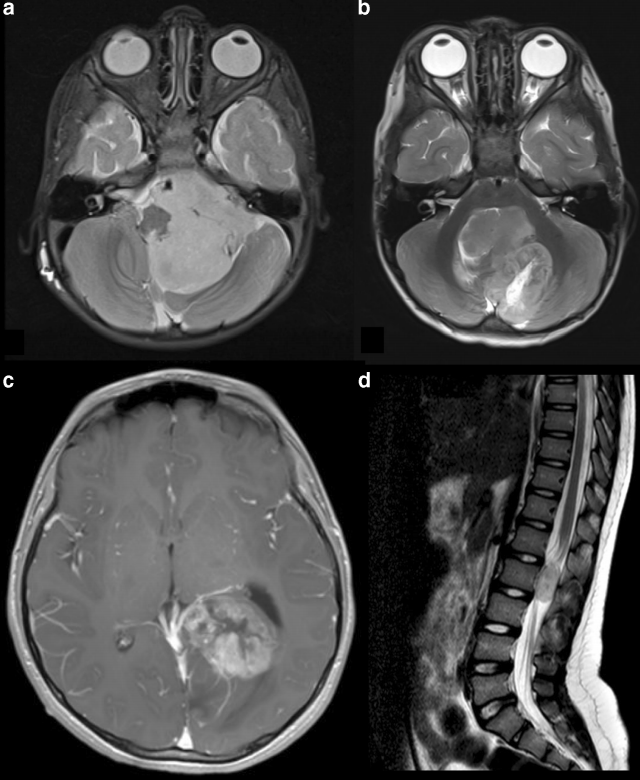

室管膜瘤可以出现在神经轴的任何位置,在任何年龄组,尽管它们在儿童中更常见,占全部儿童中枢神经系统肿瘤的6%-10%,在男性中更常见。在儿童中,70%的室管膜瘤出现在后颅窝,25%在幕上,其余在脊柱。治疗儿科室管膜瘤的基础是较大限度的顺利手术切除,然后才是放射治疗。

可采用中线四室管膜瘤手术采用俯卧位枕下开颅。肿瘤通过端部入路进入,尽量避免小脑蚓部。尾部肿瘤的扩张几乎总是可以在不切除C1的后弓的情况下切除。在接近邻近小脑梗和齿状核的肿瘤周边时,避免使用腔室吸引器。手术结束后,在高倍镜下检查肿瘤腔体,以确保切除完整。有时肿瘤会附着在四脑室底部或有侵袭性;这被仔细地刮到脑组织的其他部分,注意不要损害这个生动的表面。人们早就认识到EOR与室管膜瘤的预后密切相关。在1975年至1989年接受治疗的80例患儿中,据报道,GTR组5年PFS为51%,OS为75%,次全切除组为26%,OS为41%。在另一组92例在相似时间段接受治疗的患者中,GTR患者10年的PFS和OS分别为57.2%和69.8%;切除不完全的占11.1%和35.2%。较近,在对153名室管膜瘤患儿、5年PFS和OS进行适形放疗的St. Jude试验中,125名接受GTR的患者中,适形放疗分别占81.5%和93%。